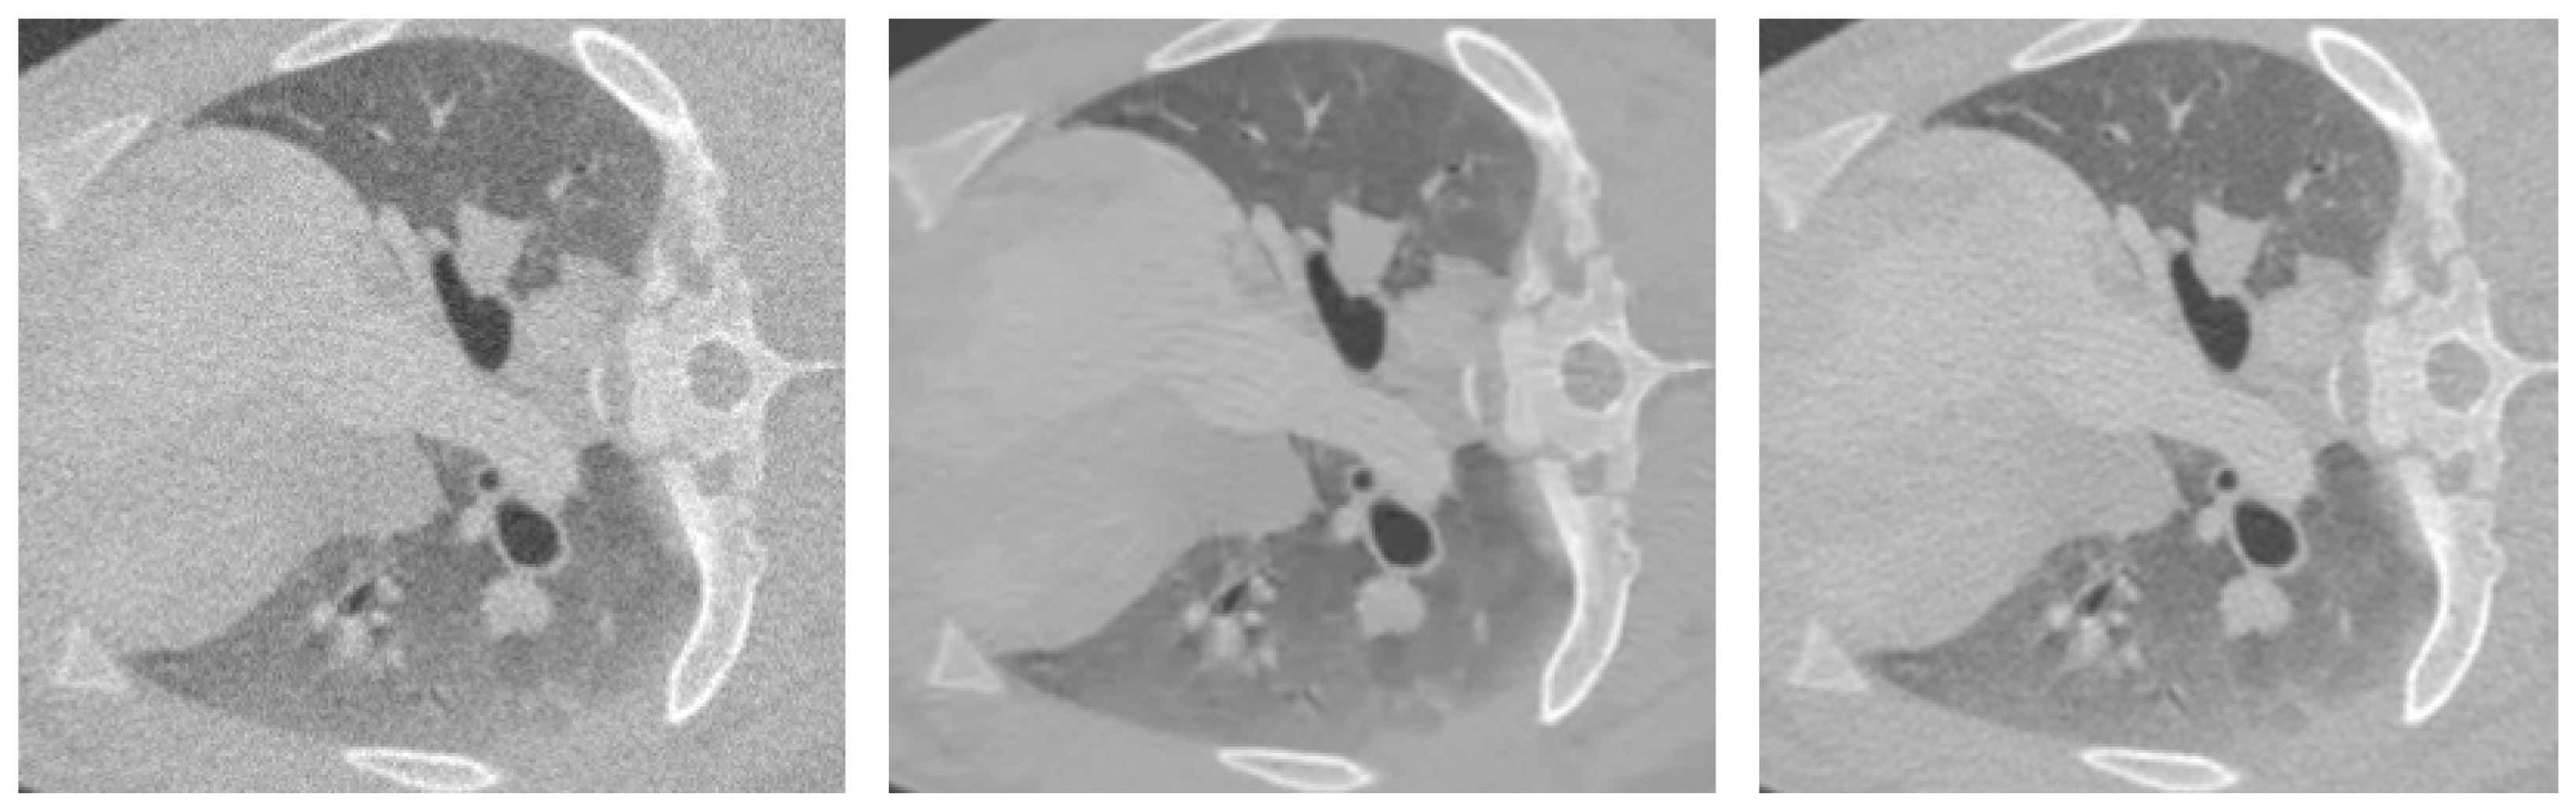

4.3. Subjective Inspection

In addition to objective quality metrics, we provide a subjective visual example in Figure 2 illustrating the model’s effectiveness in correcting artifacts and restoring image quality degraded by simulated conditions. Visual inspection against the reference standard reveals that our method has enhanced capability to reproduce fine textures and anatomical structures.

Figure 2. Comparison of image quality across different dose levels and reconstruction. The 20 mA image (left) shows degradation from the low-dose simulation; the reconstructed 80 mA image (middle) demonstrates the recovery achieved by the proposed noise correction model; and the 80 mA image (right) serves as the high-quality reference. The window level and window width used in this example are −875 and 4298, respectively, representing a full dynamic view in this case.